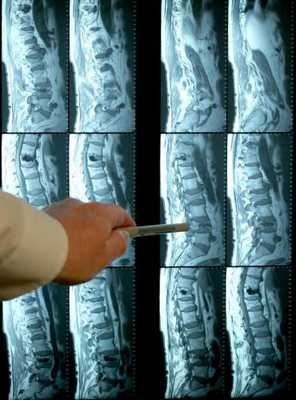

- Рентгенография. Делают несколько раз в год. При этом смотрят снимки при разном положении тела больного, чтобы получить результаты в разных проекциях. С помощью снимков возможно определить угол искривления, а также обследовать состояние позвонков.

- МРТ. Более информативен при патологиях хрящей и мягких тканей.

Одна проверка с наклоном вперед дает возможность обнаружить сколиоз, но не дает возможность обнаружить врожденные искажения позвонков. По этой причине используются лучевой способ диагностики.

Рентгенография позвоночника

Эта методика выявления является простым и общедоступным. Благодаря ему можно увидеть присутствие деформации позвонков, дать оценку степени искривления позвоночника. Рентгеновское обследование делают в двух проекциях: с боку и задне-передней. Если доктор поставил диагноз - врожденный сколиоз, ребенку дается направление к детскому ортопеду для последующей диагностики.

Компьютерная томография

Благодаря компьютерной томографии, кроме мягких тканей есть возможность увидеть еще спинномозговую жидкость, нервные корешки, но появляется шанс детального рассмотрения твердых тканей-костей. Среди преимуществ компьютерной томографии можно выделить то, что она дает точнейший снимок мельчайших деталей позвоночника, каждый тончайший слой. Кроме этого доктором может быть назначена трехмерная компьютерная томография для получения максимально точной картины и оценки позвоночника.

Магнитно-резонансная томография (МРТ).

Полагают, что благодаря МРТ появляется возможность более точной оценки состояния мягких тканей, по этой причине такое исследование получило применение для анализа патологий спинномозговой жидкости. Суть метода состоит не в рентгеновском излучении, а в создаваемом аппаратом мощнейшем магнитном поле, потому больные с имплантированными устройствами (искусственными суставами, кардиостимуляторами и пр.) имеют абсолютные противопоказания.

Рентгенография позвоночника выполняется в положении стоя и лежа в 2-х проекциях. На основании полученных спондилограмм производится расчет величины искривления по методике Фергюссона или Кобба, определение индекса стабильности позвоночника. Для более детального обследования интересующего отдела позвоночника может применяться рентгеновская томография, MРТ или КТ позвоночника, миелография. Для обследования и динамического наблюдения детей предпочтительнее применять нелучевые методы исследования, например, компьютерную оптическую топографию. Обязательным компонентом диагностики сколиоза у детей является фотографирование ребенка с различных точек на всех этапах наблюдения.